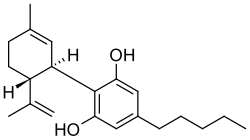

Let's start with some background on marijuana chemistry. Relevant chemicals in marijuana fall into two broad classes: cannabinoids (which in plants are specific to the Cannabis genus) and terpenoids (which are widespread in many plants).[7][8] Humans and other animals, produce endocannabinoids, which are different than but in the same chemical class as those cannabinoids found in cannabis. The main psychoactive chemical in marijuana is tetrahydrocannabinol (THC). Another important cannabinoid is cannabidiol (CBD), which is not psychoactive but has many claimed health benefits. Terpenoids in cannabis include ocimene, myrcene, β-caryophyllene, limonene, pinene, myrcene, linalool.

Reality: Cannibinoid receptors are activated by endocannabinoids,![]() i.e., cannibinoid chemicals that are naturally produced by the human body (e.g. arachidonoylethanolamine). Activation of cannibinoid receptors causes several physiological functions including gastrointestinal activity, cardiovascular activity and bone growth.[78][79]